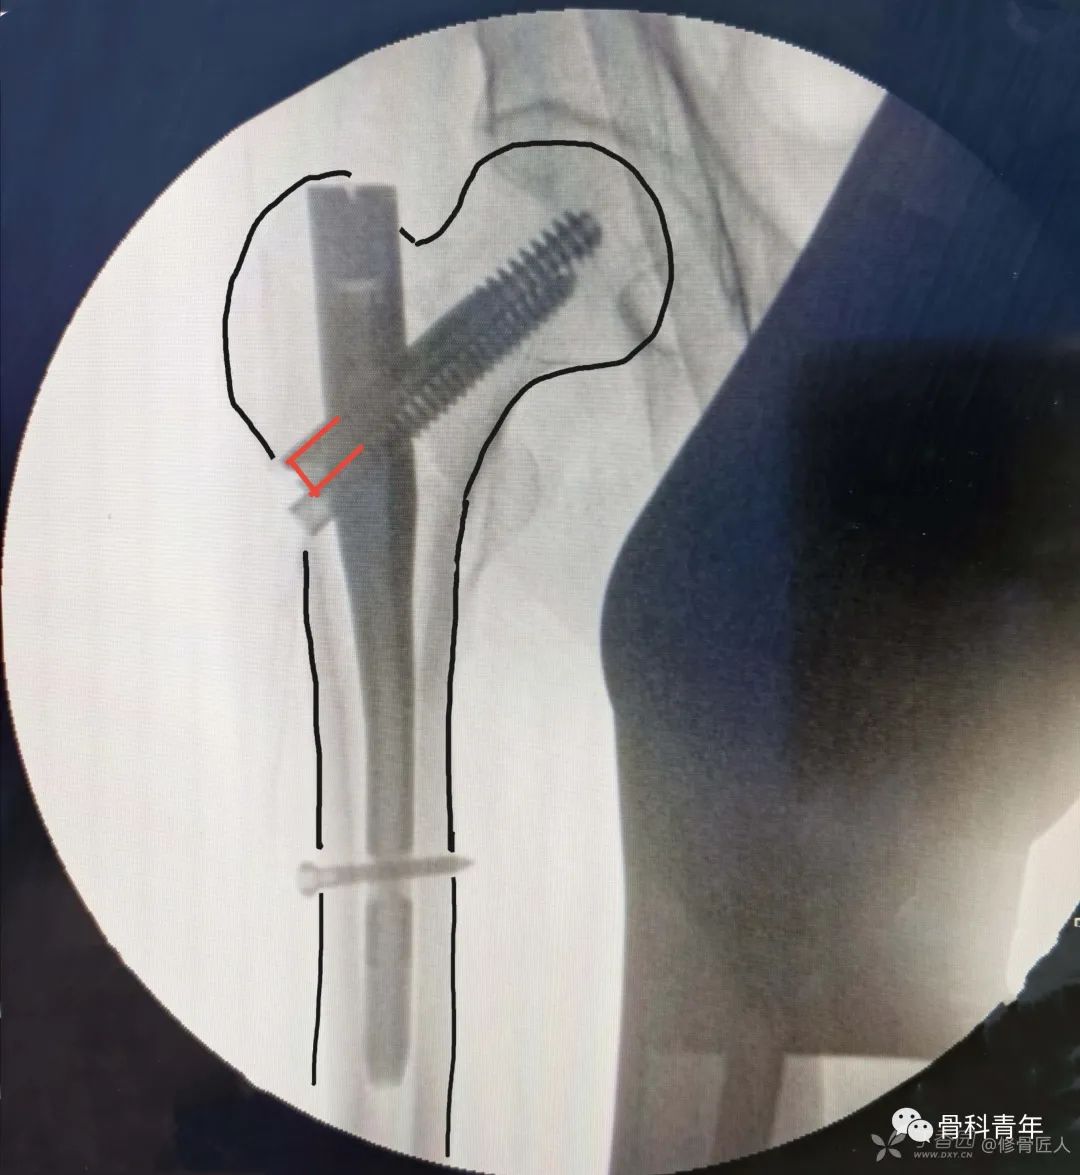

头颈钉露出皮质3-5mm

髓内钉需要保证头颈螺钉的尾部在股骨外侧皮质至少露出3-5毫米,这样在骨折愈合的过程中出现头颈骨块进一步塌陷时,头颈螺钉才容易向外滑动。

相反,如果头颈螺钉的尾部进入了股骨外侧皮质的内侧(髓腔),在骨折进一步塌陷的过程中,外侧皮质上的钉孔就可能与头颈螺钉的尾部不匹配,导致向外滑动受阻、嵌顿,从而极大的增加头颈螺钉穿透关节面进入髋关节的风险。